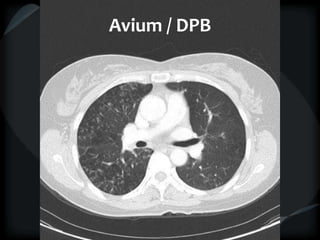

Avium / DPB

 Centrilobular nodule and ectasia

● M. avium, DPB